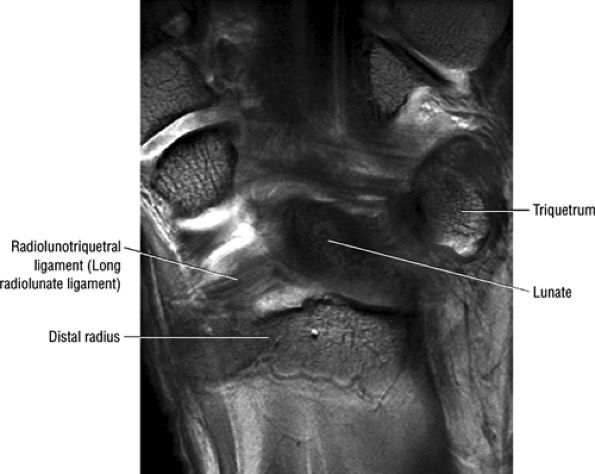

The radioscaphocapitate ligament and the radiolunotriquetral ligament, also sometimes referred to as the long radiolunate ligament, are visualized volarly and extend from the radial styloid in an ulnar-distal direction. These fibers are seen as parallel bands of striations. The more ulnarly located radioscapholunate ligament is usually seen in the same plane as the radioscaphocapitate and radiolunotriquetral ligaments and is a less substantial structure compared with the other volar extrinsic carpal ligaments. The proximal portion of the radiolunotriquetral ligament is represented by obliquely directed fibers extending from the volar radius to the lunate, volar to the proximal pole of the scaphoid.

similar to the radioscaphocapitate ligament. There is an interligamentous sulcus between the radioscaphocapitate and the radiolunotriquetral ligaments on sagittal images (Fig. 10.65). The radiolunotriquetral is a strong ligament that stabilizes the proximal carpal row on the radius and should be differentiated from the radioscapholunate ligament.

FIGURE 10.64 ● The radiolunotriquetral or long radiolunate ligament. This ligament acts as a volar sling for the lunate. Coronal T1-weighted arthrogram.